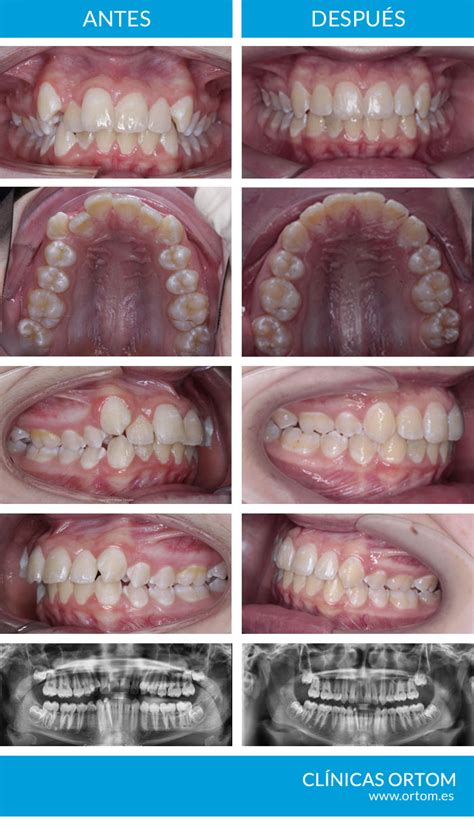

Hoy os explico un caso donde podéis ver el antes y después de un tratamiento de ortodoncia para el que se ha requerido la extracción de alguna pieza dental.

Una vez finalizado el tratamiento conseguimos los objetivos marcados:

- Espacios de extracciones perfectamente cerrados: En todos los casos el espacio de las extracciones queda completamente cerrado y no se vuelve a abrir con el paso de los años. Sin riesgo de que vuelvan a abrirse con el tiempo.

- Corrección de la protrusión de los dientes superiores: Incisivos superiores en posición correcta y no salidos o adelantados. Llevar los incisivos superiores a su posición correcta ya que estaban al comienzo muy adelantados.

- Alineamiento correcto de los dientes superiores: Un alineamiento correcto.

- Corrección de la línea media y mejora de la sonrisa: Centrar la línea media superior hacia la derecha del paciente y que ésta coincidiese con la línea inferior.